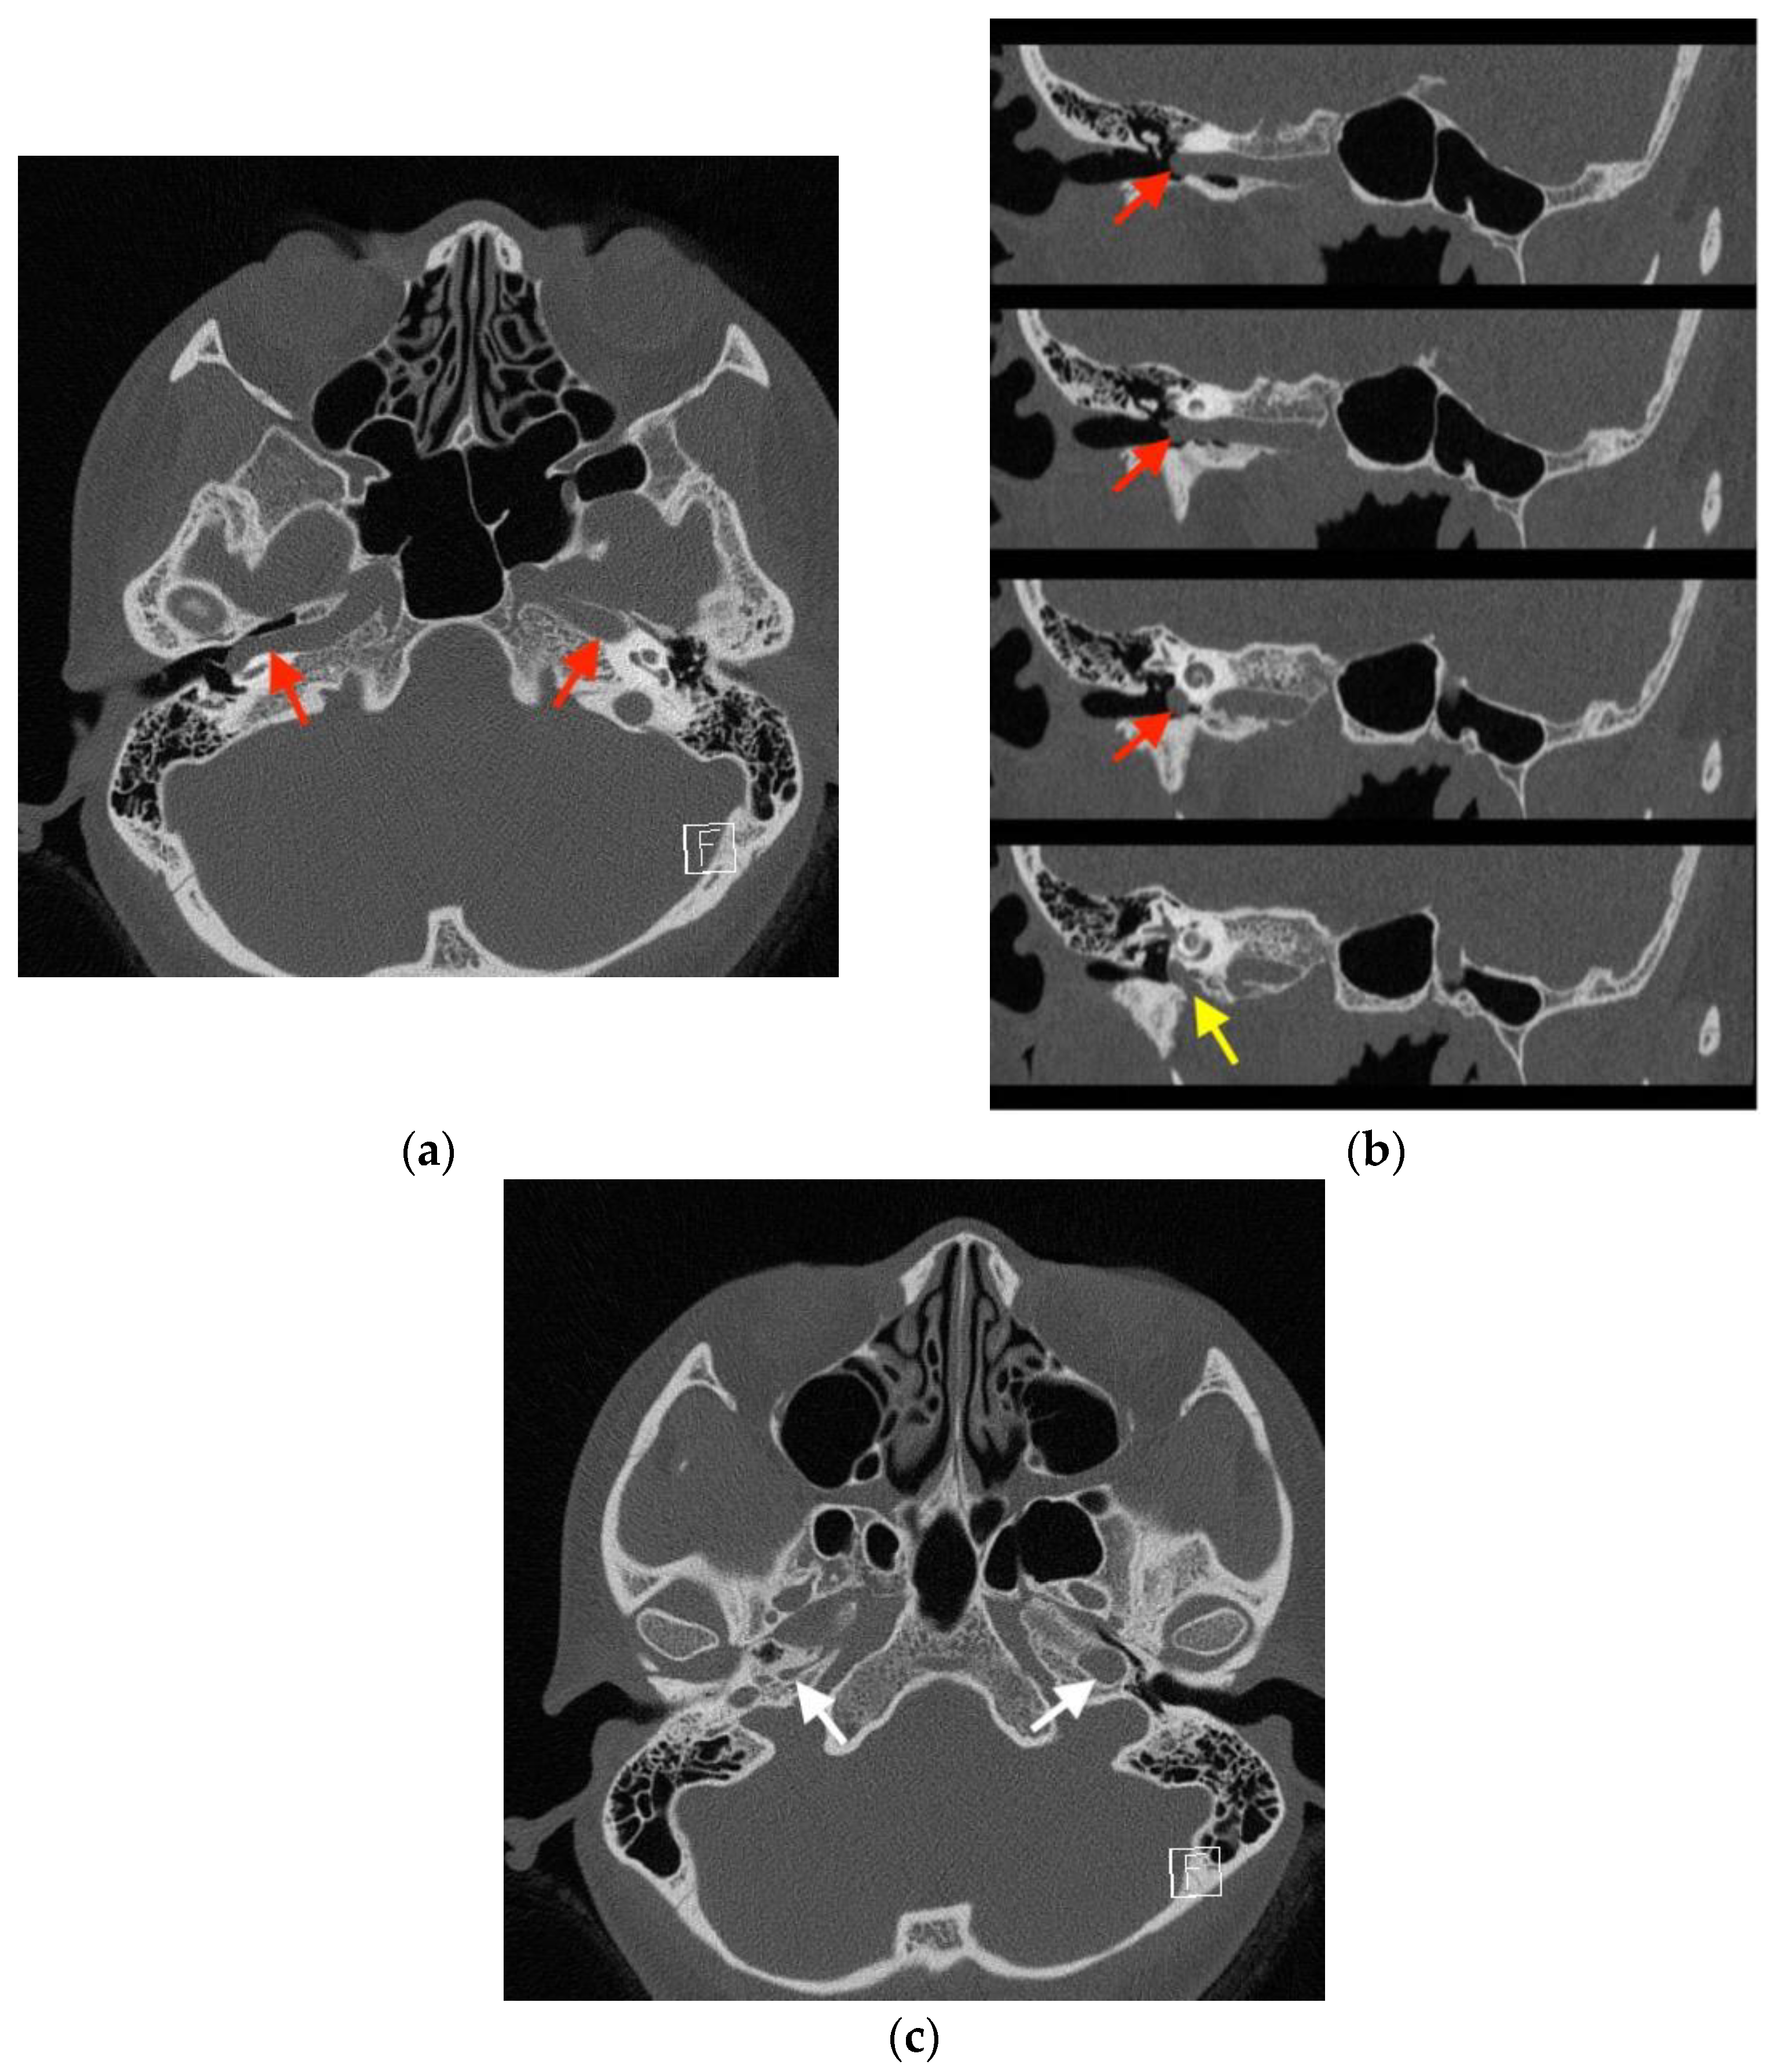

Imaging studies were subsequently performed to assess the etiology of the mass in her tympanic cavity. Unenhanced high-resolution computed tomography (HRCT) of the temporal bone revealed lateral bulging of the right ICA to the inferomedial portion of the right tympanic cavity without a bony covering, an enlarged right inferior tympanic canaliculus, and a hypoplastic right carotid canal (Figure 3). However, no other obvious abnormalities were noted in the right external auditory canal (EAC), middle ear, inner ear, and internal auditory canal (IAC). The EAC was patent and normal in configuration. The ossicles were normal in structure. The tympanic cavity and mastoid cells were clear. The configuration of the cochlea, vestibule, and semicircular canals was normal. No obvious abnormalities were noted in the IAC, petrosal apex, and cerebellopontine angle (Figure 4). Gadolinium-enhanced magnetic resonance imaging (MRI) of the head also revealed lateral bulging in the right ICA to the right tympanic cavity (Figure 5). Serial imaging studies indicated a diagnosis of right aICA.

Figure 3.

High-resolution computed tomography (HRCT) of the temporal bone, indicating a diagnosis of right aberrant internal carotid artery in the middle ear (aICA). (a) In the axial view, HRCT revealed a normal left internal carotid artery (ICA) (red arrow on the patient’s left) and lateral bulging of the right ICA to the right of the tympanic cavity without a bony covering (red arrow on the patient’s right). (b) The oblique view demonstrated the lateral bulging of the right ICA to the right of the tympanic cavity (red arrows) and the enlarged right inferior tympanic canaliculus (yellow arrow) through which the aICA (inferior tympanic artery portion) passes. (c) In the axial view, a normal left carotid canal (white arrow on the patient’s left) and a hypoplastic carotid canal (white arrow on the patient’s right) were observed. The aforementioned findings from HRCT indicated a diagnosis of right aICA.

When a red pulsatile mass is observed in the tympanic cavity, a differential diagnosis of vascular malformations in the tympanic cavity will include glomus tumor [2], hemangioma [1], and dehiscent high jugular bulb. A differential diagnosis is performed with a combination of HRCT, MRI, and magnetic resonance angiography [1,2,7]. aICA results from embryological agenesis of the cervical segment of the ICA and collateral flow through the embryonic inferior tympanic artery. aICA indicates an enlargement of the inferior tympanic artery anastomosing with an enlargement of the caroticotympanic artery when the cervical segment of the ICA fails to develop. Thus, aICA follows the course of the inferior tympanic artery and reverses that of the caroticotympanic artery. The inferior tympanic canaliculus is, therefore, much larger than normal. The aICA, after coursing through the hypotympanum, enters the horizontal carotid canal, bypassing the absent vertical carotid canal [8]. Based on the aforementioned variation in embryological development, aICA can be identified via HRCT by the following features: an intratympanic mass, an enlarged inferior tympanic canaliculus, the absence of the vertical segment of the ICA canal, and the absence of bone covering the tympanic portion of the ICA [5]. These features were all observed in our case (Figure 3). aICA is occasionally combined with cystic cochleovestibular anomaly [3], persistent stapedial artery [9], and duplicated ICAs [10], but these anomalies were not present in our case.